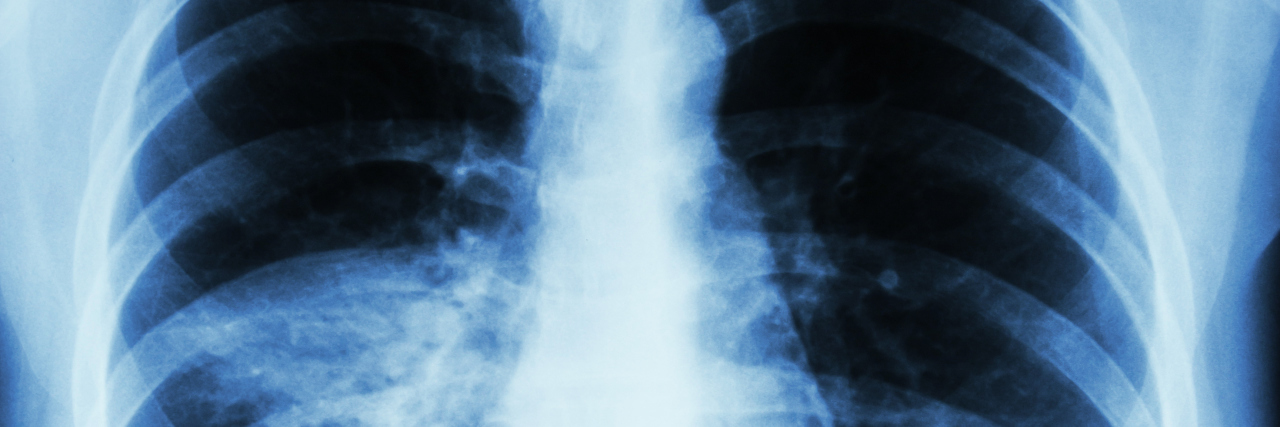

I heard from my GP today that you showed up for a group picture with my stomach. I am not sure how that happened, since I was looking to capture the elusive answer to my severe nausea. Somehow, the camera — the incredibly expensive one called Computerized Axial Tomography or CAT scan — caught an image of your bottom lobes.

They found nothing wrong with my gut. However, some tiny nodules, referred to as ground-glass densities, were found on both of your lobes. I will keep you posted in three months from now when I have another scan. The GP is hoping (or perhaps I am hoping and the doctor is merely speculating) that you have had a hidden virus, infection, or inflammation that will go away on its own.

We took pictures of just you! Thirty adult years of not eating red meat, not smoking, not drinking alcohol, and lots of swimming in lap pools have kept me relatively healthy. In other words, no hidden infections, no pneumonia, no viruses. The ground glass nodules are still there. It seems odd that you are harboring uninvited, unwanted aberrations.

The good news: nothing new appeared and the original ones have neither thickened nor grown. I have a pulmonologist, and he said I have nothing to be worried about.

It’s been two years. I had another CAT scan without contrast just to check up on you. It seems a few of your nodules are larger. One of them, a 1.2 cm nodule in your medial left upper lobe, is growing, as is one in the lower left lobe.

I have just had another CAT scan, and the results read, “There are again noted areas of increased density and ground glass opacity.” Guidelines recommend a tissue sampling. In that case, it means major surgery, since these nodules are deep, deep within your recesses.

I brought the CAT scan and results of a positron emission tomography (PET) scan the surgeon ordered before I saw him. The PET scan said there was “no significant FDG uptake,” which essentially means no evidence of malignancy. The surgeon looked at the latest CT scan and said, “I am 80 percent certain you have cancer. When would you like to schedule surgery?”

Thank you for all that you do. Thank you for giving me 115 percent capacity prior to surgery, so I can still breathe deeply after a chunk of lung has been removed and biopsied. I want you to know the area of density they removed was indeed non-small cell adenocarcinoma.

The lymph nodes are clean, which means the cancer is considered stage 1. We go back to the surgeon in six months, and also visit an oncologist with whom I can build a long term relationship. It turns out these ground glass nodules are insidious! You still have six of them, and they grow slowly.